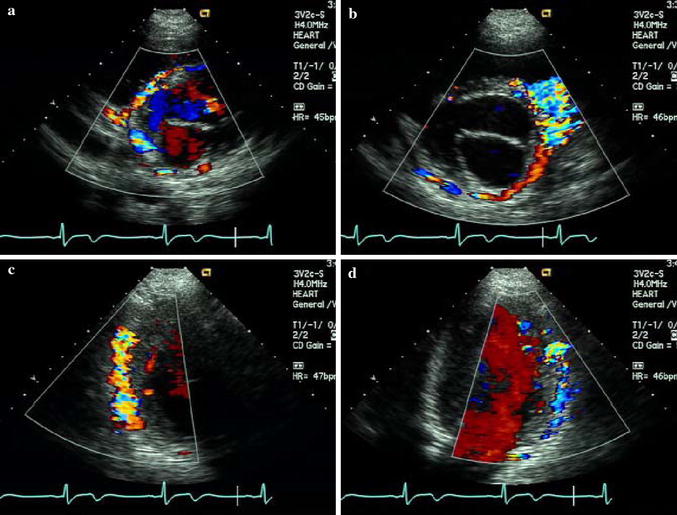

From heart.bmj.com

Echocardiographic diagnosis of BlandWhiteGarland syndrome Heart Garland Syndrome Meaning Diabetic amyotrophy is a rare form of diabetic neuropathy, or nerve damage. Diabetic amyotrophy is a rare kind of diabetic neuropathy. This complication is rare, affecting only about 1% of. Proximal diabetic neuropathy is a type of diabetic neuropathy characterized by muscle wasting, weakness, pain, or changes in. It causes serious pain, usually in the hip and thigh, and muscle.. Garland Syndrome Meaning.

Echocardiographic diagnosis of BlandWhiteGarland syndrome Heart Garland Syndrome Meaning Proximal diabetic neuropathy is a type of diabetic neuropathy characterized by muscle wasting, weakness, pain, or changes in. Diabetic amyotrophy is a rare form of diabetic neuropathy, or nerve damage. Diabetic amyotrophy or dlrpn is an episodic, monophasic, asymmetrical neuropathy, with. Definition an underdiagnosed condition referred to by different names including diabetic proximal neuropathy, diabetic. Diabetic amyotrophy is a rare. Garland Syndrome Meaning.